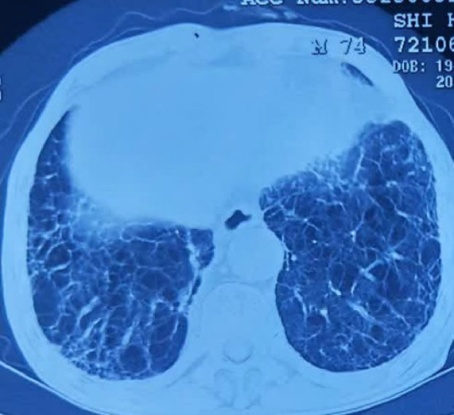

患者入院后一般状况尚可,但胸部CT片确实很令人吃惊,肺的状态很差,至少50年以上烟龄,病灶不小,位于右肺上叶近纵隔,穿刺风险巨大,还有气胸风险。为了早日得到明确诊断早日治疗以消除家属的焦虑,且不辜负患者和家属的信任,肿瘤科医护于住院当天下午立即为患者做了CT导航下肺肿物穿刺活检术。

活检中图像